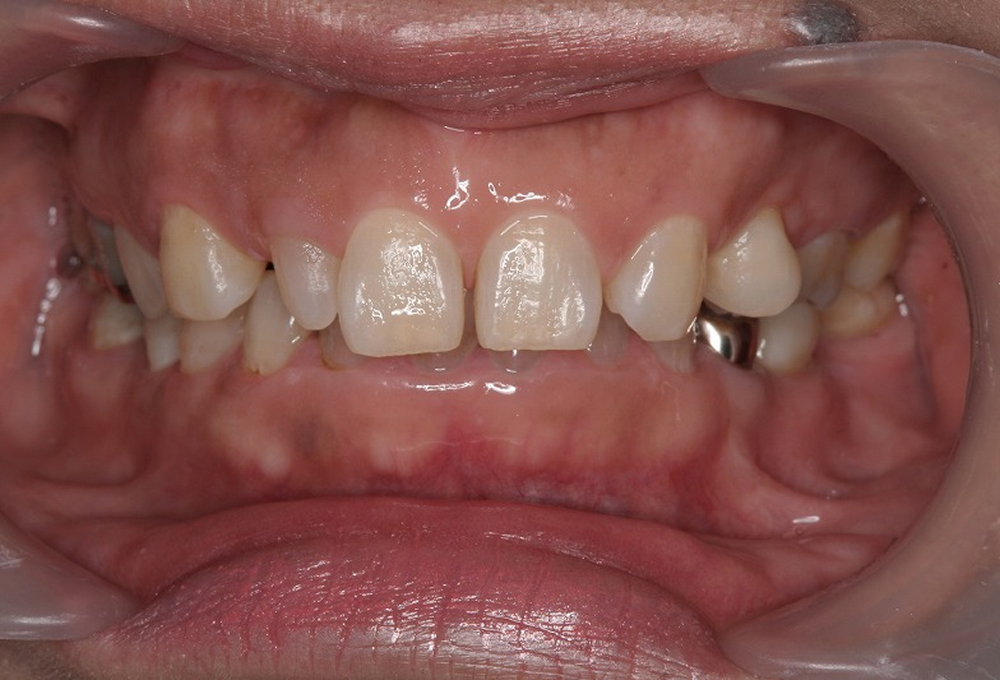

①術前